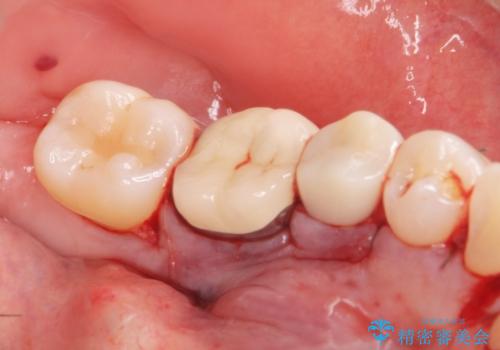

骨隆起除去

- 骨隆起が舌にあたり不快感があるので骨隆起をとりたくて来院。

静脈内鎮静麻酔下で骨隆起を除去を行いました。

骨隆起がなくなり不快感がなくなり大変満足して頂けました。